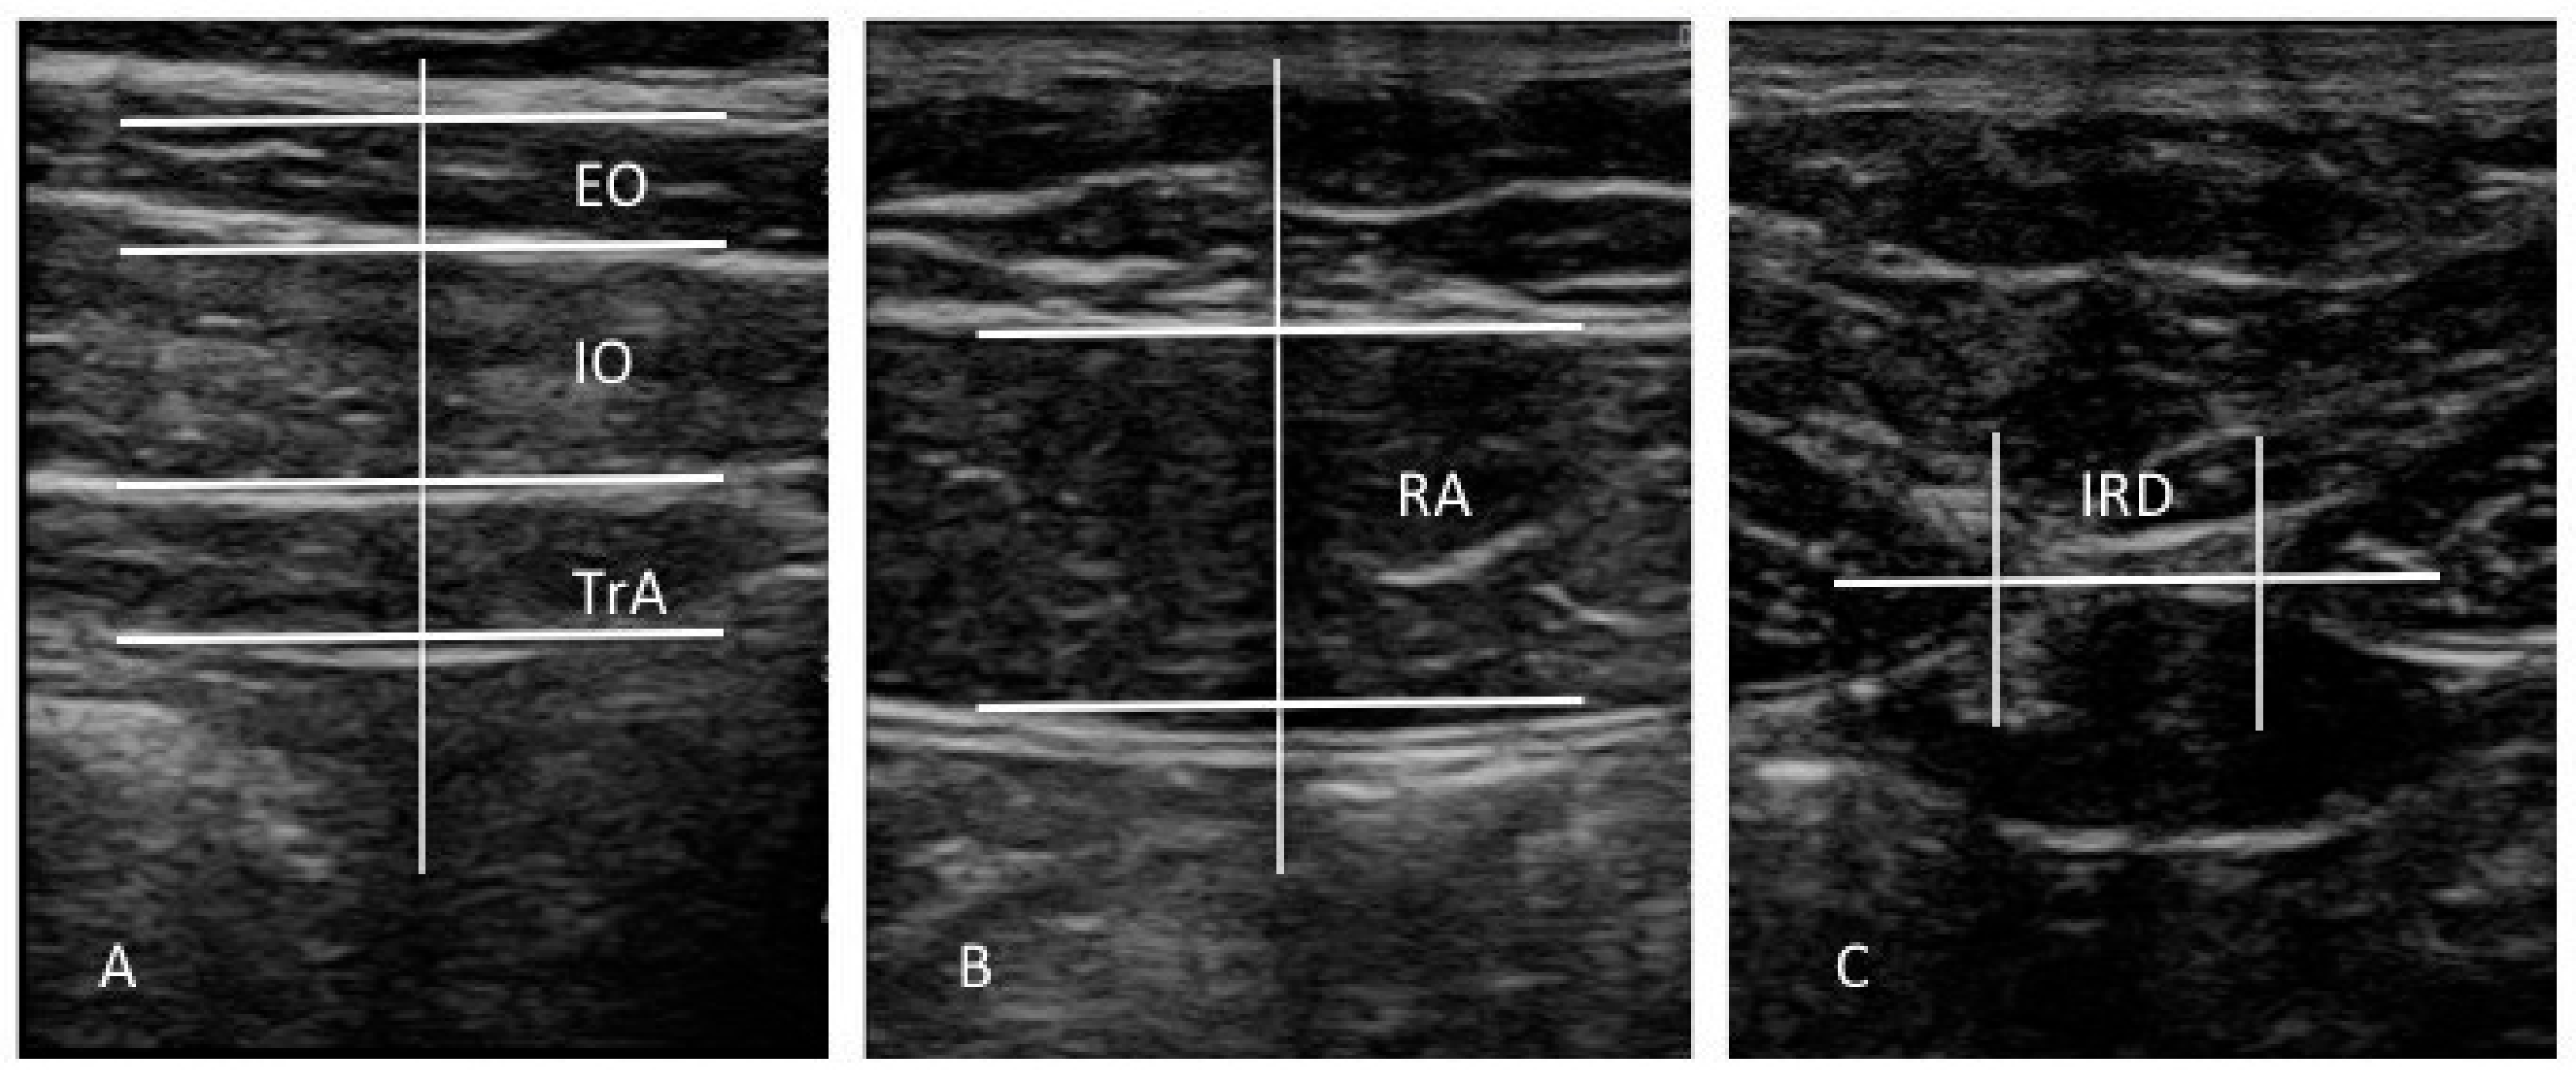

All evaluations were carried out by a single operator (J.A.P.), a specialized physical therapist with 3 years of RUSI experience. The evaluator was not blinded to both groups during data evaluation [12]. A diagnostic ultrasound tool (Toshiba Aplio 500 Platinum; Toshiba American Medical Systems, Tustin, CA, USA) with a 7–14 MHz range linear transducer (18L7 PLT-1204BT type; 40 mm footprint) was used for B mode ultrasound imaging. According to the protocol of Whittaker et al. [12], ultrasound images of the EO, IO, and TrAb muscles were carried out with the subjects in supine position, with a cross-reference point placed between the iliac crest and the inferior border of subcostal line and the midaxillary line (Figure 1A and Figure 2A); RA muscle was aligned with the umbilicus (Figure 1B and Figure 2B); and IRD was measured just under the umbilicus (Figure 1C and Figure 2C). Previously, anatomical landmarks were located by means of palpation and a dynamic ultrasound evaluation following the methodology proposed by Whittaker et al. [12], which showed excellent interday and interexaminer reliability (ICC = 0.92–0.99) for these RUSI measurements. The mean of 3 repeated values was collected for each measurement at the end of expiration, maintaining the transducer at the same point and with the same pressure (only the pressure generated by the weight of the transducer). IRD was only evaluated in the midline. The rest of the measurements were obtained at the left and right sides. Muscle thickness was measured at the center on the image and considered as the distance (cm) between the inside caliper lines of each muscle border. EO thickness was perpendicularly measured inside the superficial connective tissue and the connective tissue located between EO and IO. IO thickness was perpendicularly measured inside the connective tissue located between EO and IO and between IO and TrAb. TrAb thickness was perpendicularly measured inside the deep connective tissue and the connective tissue located between IO and TrAb (Figure 2A). RA thickness was perpendicularly measured inside the superficial and deep connective tissues (Figure 2B). IRD was described as the horizontal distance between both RA muscles (Figure 2C) [12]. ImageJ software (version 2.0; US National Institutes of Health, Bethesda, MD, USA) was employed to measure all the images offline [28].

Figure 2.

Muscle thickness and IRD measurements of the abdominal wall. EO, external oblique; IO, internal oblique; IRD, interrecti distance; TrA, transversus abdominis; RA, rectus abdominis.